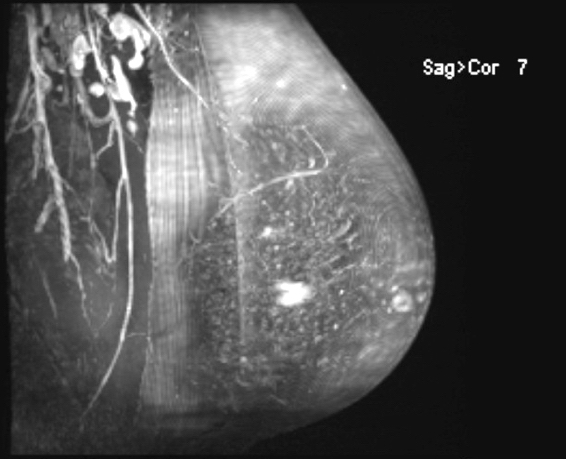

- MRI:

- Preferred modality for abdominal wall and extraabdominal tumors

- Heterogeneous iso to hyperintense to skeletal muscle on T2, isointense to muscle on T1

- Nonenhancing linear bands (Band sign) can be seen in 60 - 90% of cases

- Moderate to marked enhancement after gadolinium based contrast (Radiographics 2016;36:767)